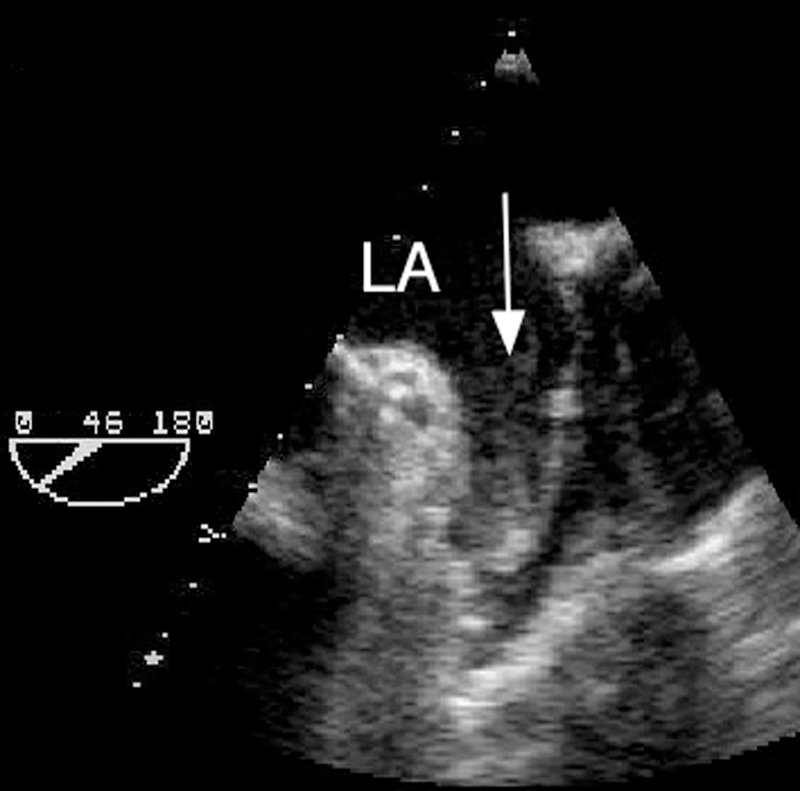

فحوصات تشخيصية لبعض امراض القلب والشرايين التاجية